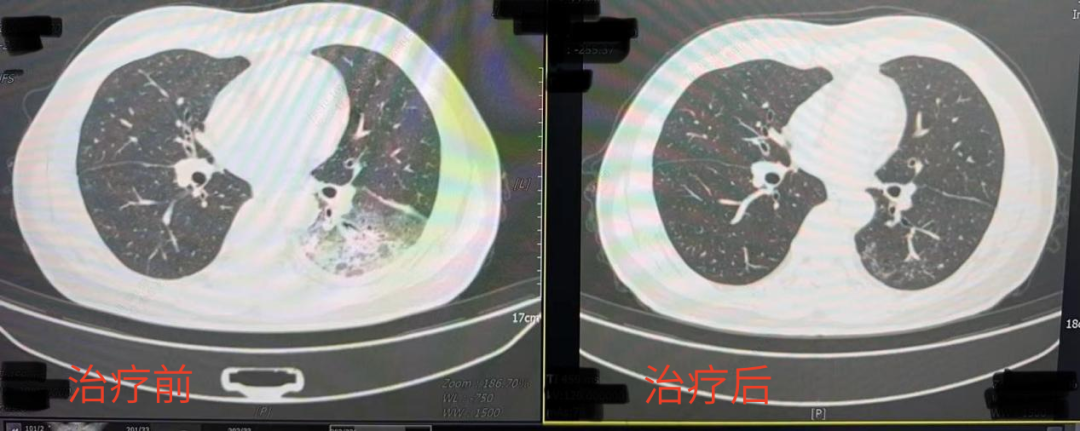

嗜肺军团菌感染“白肺”治疗前后。来源:成都市第五人民医院

“我这条命都是空调给的”,随着气温逐步升高,不少人选择开空调纳凉。近日,成都市民李先生在开启尘封一年的空调后,竟意外患上了严重的肺炎,左肺“白”了接近一半。

据报道,李先生开了3天空调后,出现了肌肉酸痛、头痛、发热和咳嗽等症状。起初,他以为是吹空调吹感冒了,但自行服用感冒药后病情并未好转,反而愈发严重。经过医生确认,引起肺炎的“罪魁祸首”是嗜肺军团菌。